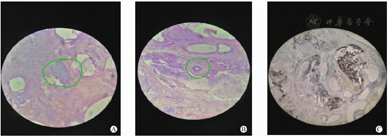

女,孕期彩超排畸检查发现骶尾部肿物,随胎儿发育增大,胎龄38+2周剖宫产,体重3. 4 kg,胎盘、羊水、脐带均正常。查体:发育、营养好,心肺腹无殊。肢体肌张力正常,新生儿反射存在。骶尾部可见一肿物蔓延至整个臀部(图1A) ,大小约15 cm × 6 cm,高于周边组织。辅助检查:动脉血气分析、肝肾功能、甲状腺功能、血糖、电解质、血常规、凝血常规等在正常范围,遗传代谢病筛查无异常。MRI平扫+增强:骶尾部巨大囊实性占位,考虑畸胎瘤(图1B)。入院后住多功能婴儿暖箱,箱温保持30~ 33 ℃。禁食插胃管,吸氧,输液纠正水电解质紊乱和酸中毒,控制感染等,评估可耐受手术后予以完整切除肿瘤,采用骶部常规手术切口倒"V"形,尖顶超过尾骨,左右两侧向双臀延伸,切口暴露广,距离肛门较远,术后恢复良好。病理诊断:符合成熟型畸胎瘤(图2) ,局部皮肤溃烂结痂形成。术后给予保暖,营养支持,控制感染和皮肤护理,疼痛管理等治疗,复查AFP正常。随访1年,生长发育评估正常,畸胎瘤无复发(图1C)。

注: A为术前SCT; B为MRI显示无压脂像; C为术后1年随访。

注: A为表皮及附属器; B为脂肪、成熟神经组织; C为平滑肌组织。